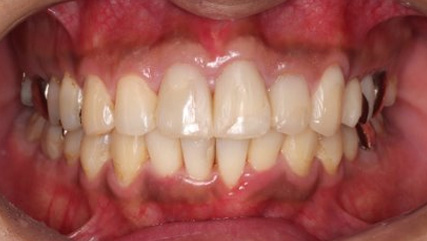

上顎前突といわれ、上顎の前歯が唇側に出ている状態を言います。

前歯が出ることで見た目の問題もありますが、口を閉じることができない、口呼吸をしてしまう、外傷などのリスクがあります。

日本人に叢生の次に多い不正咬合と言われており、自然に治ることはありません。また上の前歯が出ている事だけが気になるかもしれませんが、多くの場合、上顎の奥歯の位置に問題があることが多く、部分矯正でなく根本的な治療をした方がいい場合が殆どです。

口を閉じることができないことで、鼻呼吸でなく口呼吸をしてしまい、結果、成長期の場合顎の骨の成長を邪魔してしまうとも言われております。その他、口呼吸はアトピーなどを含むアレルギー症状の悪化、風邪を含むウイルス性の感染症にかかりやすいなどのリスクも増大してしまいます。

歯並びだけでなく全身への影響も多い為、早期の治療をおすすめ致します。